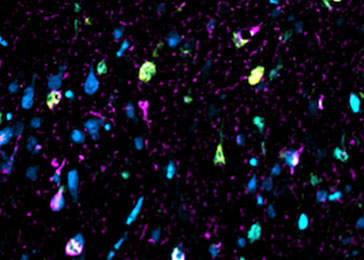

Fragments of tau protein appear as green and cyan spots amid purple spots (neurons) in brain tissue sample

Once stained with fluorescent compounds, fragments of tau protein appear as green and cyan spots amid purple spots (neurons) in brain tissue sample from a patient who had Alzheimer's disease. Samples from patients with other forms of dementia showed much less, if any, of the fragments. Image by Grinberg Lab